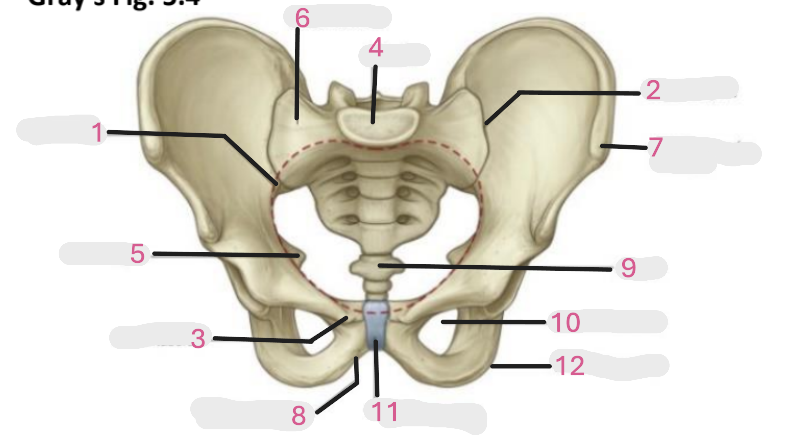

Where is the pelvic inlet

1

Where is the sacro-iliac joint

2

Where is the pubic tubercle

3

Where are the S1 body

4

Where is the ischial spine

5

Where is the ala of sacrum

6

Where is the anterior superior iliac spine

7

Where is the ischiopubic ramus

8

Where is the coccyx

9

Where is the obturator foramen

10

Where is the pubic symphysis

11

Where is the ischial tuberosity

12